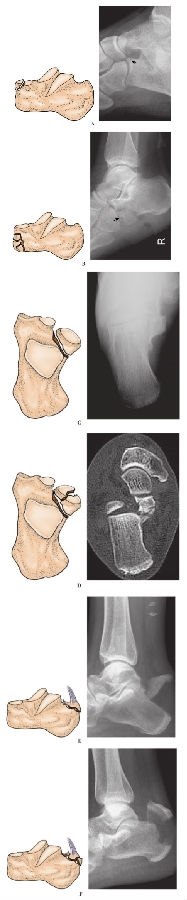

3、AO/OTA分型:

目前,由于AO骨折分型系统已发展成一套科学规范被普遍应用并被普遍接受的分型系统,对骨折的诊治有一定的指导作用,近年来已逐渐成为人们广泛使用的分型标准(图15)。

图15跟骨骨折OA/OTA分型

A. A型 跟骨撕脱或跟骨前部或跟骨结节骨折A1 跟骨前部骨折:A1.1 非粉碎骨折

B. A型 跟骨撕脱或跟骨前部或跟骨结节骨折A1 跟骨前部骨折:A1.2 粉碎骨

C. A型 跟骨撕脱或跟骨前部或跟骨结节骨折A2 跟骨载距突骨折:A2.1 非粉碎骨折

D. A型 跟骨撕脱或跟骨前部或跟骨结节骨折A2 跟骨载距突骨折:A2.2 粉碎骨折

E. A型 跟骨撕脱或跟骨前部或跟骨结节骨折A3 跟骨结节骨折:A3.1 非粉碎骨折

F. A型 跟骨撕脱或跟骨前部或跟骨结节骨折A3 跟骨结节骨折:A3.2 粉碎骨折

G. B型 跟骨关节外跟骨体骨折:B1 非粉碎骨折

H. B型 跟骨关节外跟骨体骨折:B2 粉碎骨折

I. C型 波及后关节面的跟骨骨折:C1 无移位骨折

J. C型 波及后关节面的跟骨骨折:C2 两部分骨折

K. C型 波及后关节面的跟骨骨折:C3 三部分骨折

L. C型 波及后关节面的跟骨骨折:C4 ≥四部分骨折